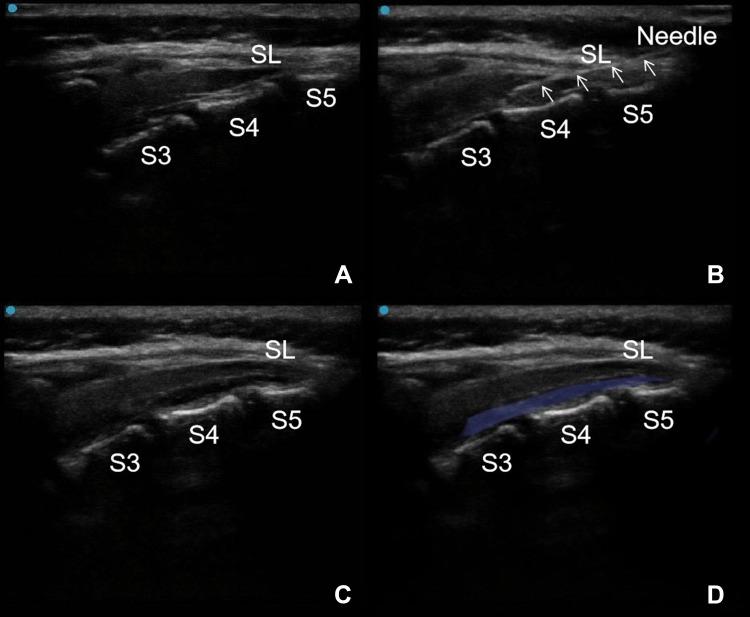

A total of 60 children undergoing laparoscopic surgery were randomly divided into two groups: GI and GC groups. The general anesthesia was induced with midazolam, propofol, sufentanil and succinylcholine in both groups. In addition, the patients were subjected to continuous sacral block with levobupivacaine in group GC. The modified protocol of continuous sacral block was divided into three steps: comprehensive lumbar and sacral vertebral canal scanning by ultrasound, catheterization and administration. The EVENDOL pain scales and pediatric anesthesia emergence delirium scales of the children were evaluated at 5 min after extubation (T), 90 min (T), and 4 h (T) after the operation. The nurses' satisfaction scores at T -T and adverse events, such as nausea and vomiting, were also recorded, after the operation.

总共60例接受腹腔镜手术的儿童被随机分为两组:GI组和GC组。两组均使用咪达唑仑、丙泊酚、舒芬太尼和琥珀酰胆碱诱导全身麻醉。此外,GC组患者接受左旋布比卡因连续骶管阻滞。改良连续骶管阻滞方案分为三个步骤:超声全面扫描腰骶椎管、置管和给药。在拔管后5分钟(T1)、术后90分钟(T2)和4小时(T3)评估儿童的EVENDOL疼痛量表和小儿麻醉苏醒期谵妄量表。术后还记录了T1 - T3时护士的满意度评分以及恶心、呕吐等不良事件。